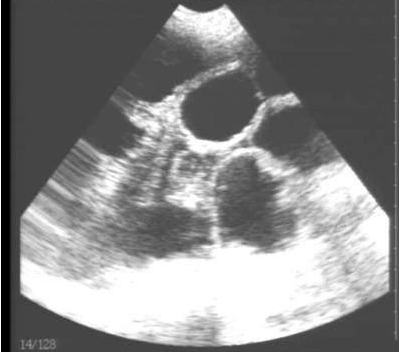

豬用B超機檢測有胎兒圖像

需要注意的是,出現云團狀必須雙側檢查加以確認.根據B超機顯示圖我們大致可以判斷孕齡.圖像呈橢圓或者卵圓形大致為30天左右孕齡;圖像呈橢圓形或者卵圓形外,有明顯發亮骨骼圖像大致為50孕齡左右;圖像囊胚消失,發亮處隱約可見竹節狀東西為成型胎兒骨骼,一般為后期80孕齡以后。一般B超機成像會出現三種顏色,白色、黑色、灰色。白色為密度較高的物體,如骨骼或者結實.黑色一般為液體,包括血液、羊水、組織間隙液體、炎癥病灶等?;疑话銥閷嵸|性物質,如肌肉。